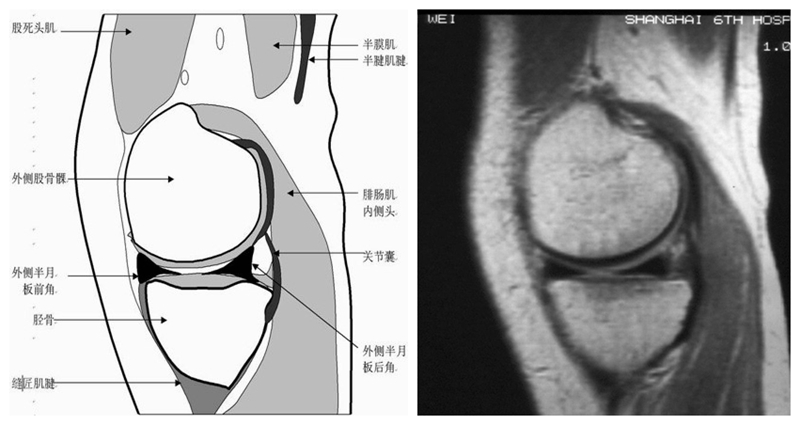

膝关节矢状面正常解剖MRI表现

可整段显像髌韧带、前后交叉、外侧韧副带结构,侧重的股胫软骨中部和半月板前后角,通常是诊断半月板撕裂或变性最为关键的断面。